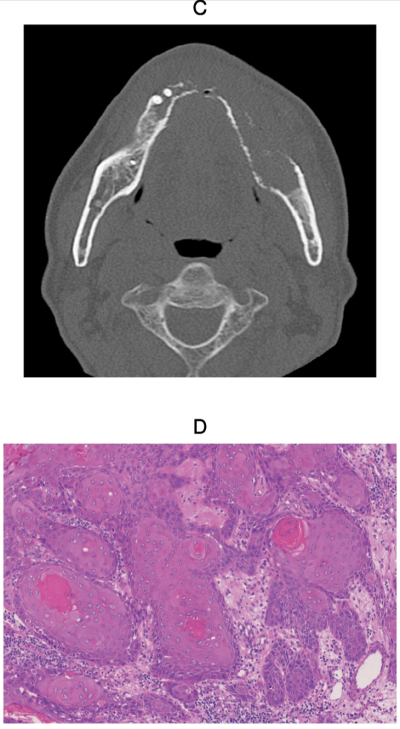

75歳の男性。下顎左側歯肉の異常を主訴として来院した。1か月前から左側下唇に軽度の知覚鈍麻を自覚するようになったという。既往歴として骨粗鬆症、糖尿病および高血圧症がある。初診時の口腔内写真、エックス線写真、CT及び生検時のH-E染色病理組織像を示す。

診断はどれか。1つ選べ。

a. 扁平上皮癌

b. エナメル上皮腫

c. 薬剤関連顎骨壊死

d. 慢性化膿性顎骨骨髄炎

e. びまん性硬化性顎骨骨髄炎